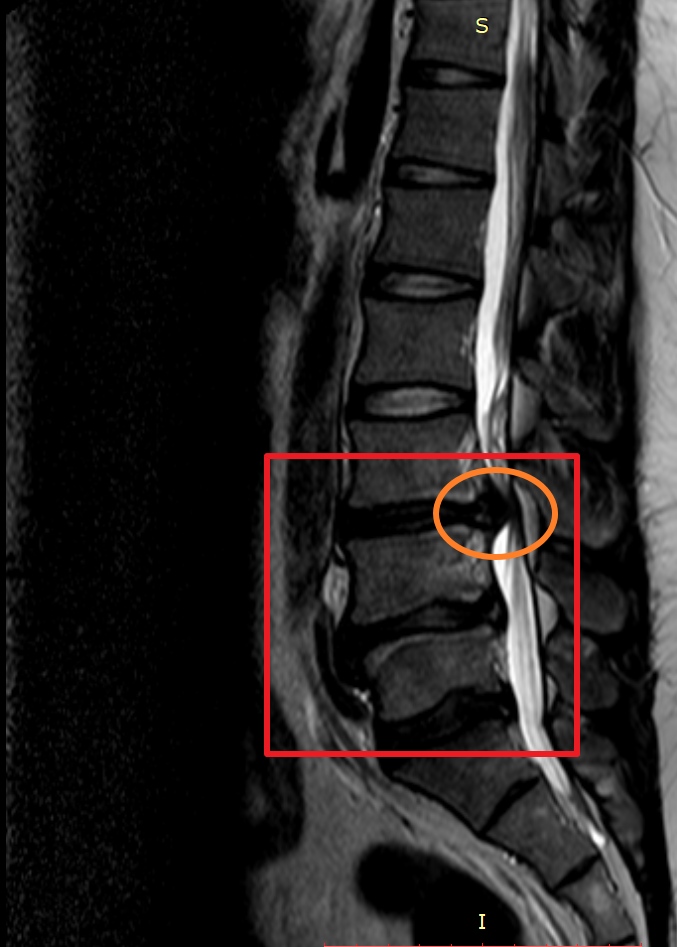

마지막으로 제가 촬영했었던 MRI 촬영 이미지를 첨부해 볼까 합니다. 이미지 순서대로 2014년, 2018년, 2020년 촬영했던 MRI 사진입니다. MRI 촬영 당시 허리디스크 상태가 좋지 않은 상황에서만 세 차례 찍었던 것이기에 이점도 고려해서 참고하시면 좋을 듯합니다.

이미지를 보시면 빨간색 네모 칸에 하얀색 기다란 세로 라인이 신경이 지나가는 부분이며 가장 바깥쪽 두꺼운 흰색 부분은 배 쪽의 지방입니다.

2014년 당시 대체로 튀어나온 허리디스크는 없으나 주황색 동그라미 부분에 엄청나게 많이 신경을 누르고 있었던 상황